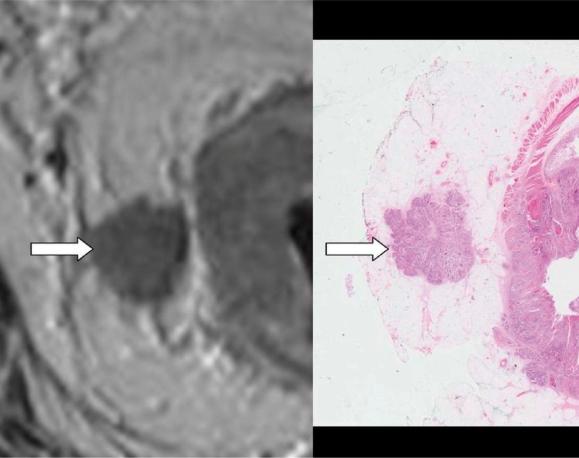

The success of pre-operative therapy over post-operative treatments means that a technique identifying prognostic factors pre-operatively is of potential benefit in modifying the intensity of pre-operative therapy according to risk of local or distant failure. Clinical trials incorporating robust and accurate assessment of prognostic factors and appropriate stratification of patients prior to therapy will enable objective comparison of treatment modalities and outcomes. Careful staging of rectal tumours results in selective pre-operative treatment strategies aimed at reducing local failure and distant failure in high risk patients.